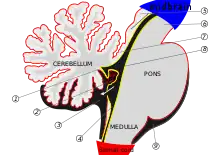

![]() | |

| T2-weighted sagittal MRI of Dandy–Walker variant (DWV) with dysplasia of the pons and cerebellar vermis in an 8-year old | |